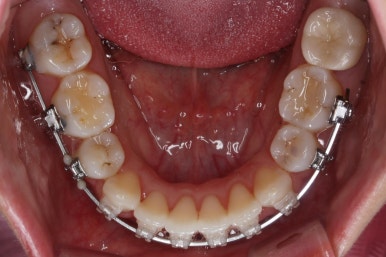

아랫니 모습입니다.

남아있는 발치의 공간이 없어졌으며 큰 이동이 없이 마무리가 되었습니다. 안쪽에는 발치공간이 다시 벌어지지 않도록 유지철사를 길게 연장해서 붙였습니다.

아래쪽의 앞니에는 잇몸뼈가 없기에 자칫 뿌리가 다 드러날 수 있는 위험한 상태였습니다.

다행히도 잇몸이 덮고 있었고 조심스레 마무리를 했기 때문에 추가적인 악화는 없었습니다. 그래도 아래앞니 쪽은 잇몸뼈가 약하기 때문에 평생 조심을 해야 한다며 거듭 말씀드리고 당부 드렸습니다.